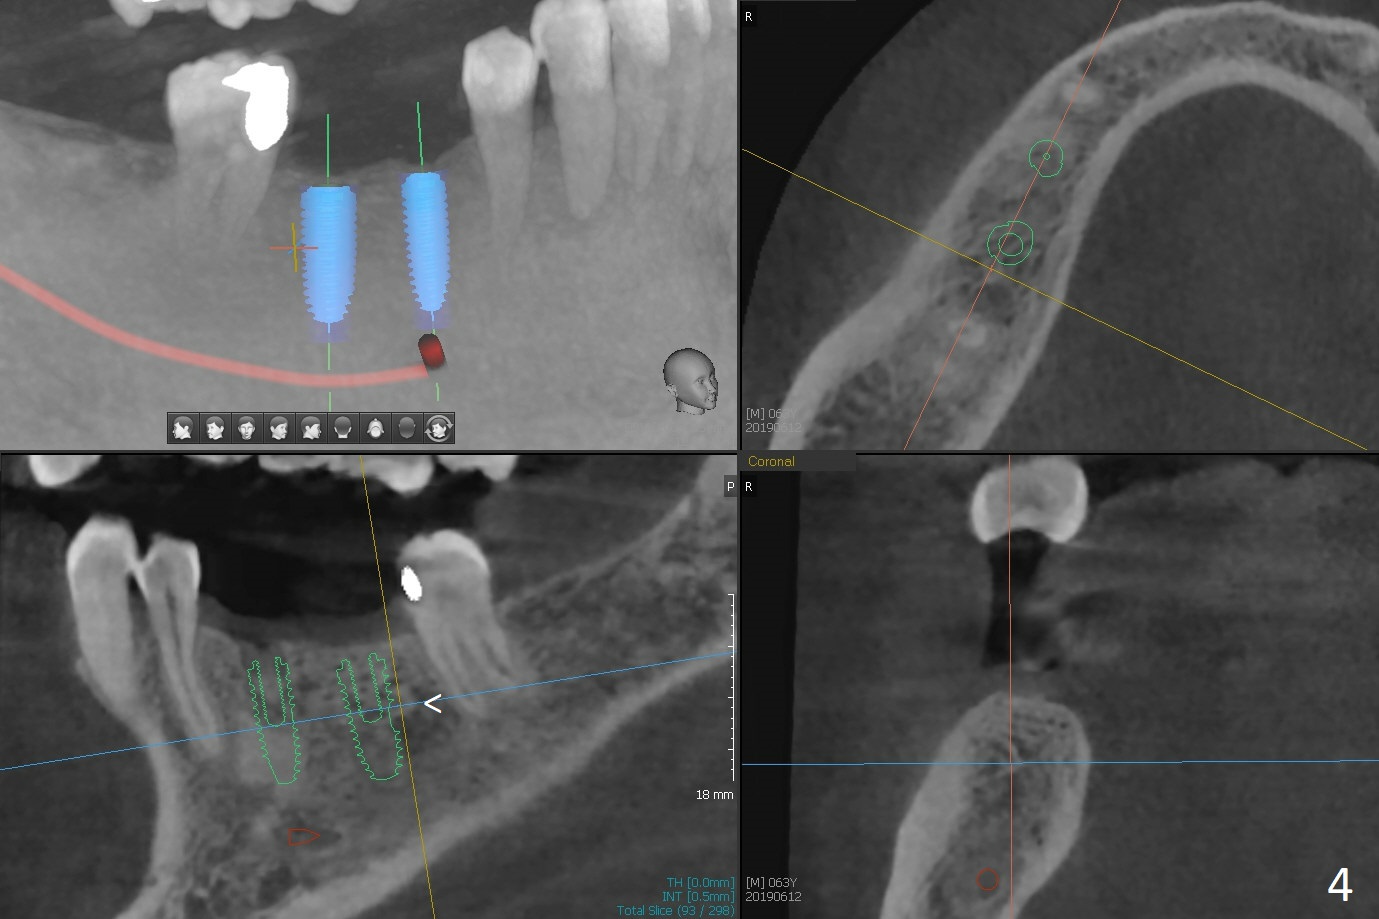

A 63-year-old man requests implants to replace a flipper at #29 and 30 (Fig.1). If torque is >25 Ncm for each implant (Fig.2,3 (2 mm bone buccolingually)), abutments will be placed immediately (using planning kit) for splinted provisional. Take photos for the flipper for a good bye party. Composite will be placed at #31 for MO leakage. Remove a small piece of residual root distal to #30 implant with curettage after osteotomy (Fig.4 <).